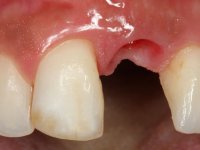

A paciente de sexo feminino de 28 anos de idade perdeu por traumatismo o incisivo central superior esquerdo. Preocupada com o seu sorriso, a paciente apareceu no consultório querendo alinhar os dentes antero-superiores para obter uma aparência mais natural. Sendo fumadora a paciente não apresentava problemas médicos dignos de registo.

A paciente apresenta um desvio da linha média superior de 6 mm para a esquerda. Resultado da ausência do incisivo central superior esquerdo, os dentes adjacentes inclinaram mesialmente para esta zona, limitando o espaço disponível para a reabilitação prostodontica. Existe uma significativa desarmonia dentária negativa no arco maxilar como resultado da ausência do 21, ausência do primeiro pre-molar com um espaço residual, significativa redução coronária do segundo pre-molar direito, migração dos dentes posteriores para os espaços não preenchidos e uma mesialização molar superior esquerda e direita com uma relação molar em Classe II. Ambos os caninos esquerdo e direito mostram uma relação Classe II na posição de inter-cuspidação máxima. A paciente apresenta uma linha de sorriso média, um biótipo gengival médio grosso, apresenta uma correcta higiene oral sem doença periodontal. Não apresenta hábitos para –funcionais. O exame radiográfico mostra uma significativa inclinação dos eixos dos dentes 11 e 22 com espaço entre a porção apical das raízes. A análise cefalométrica foi feita com o intuito de explorar a hipótese de conseguir arranjar espaço para a colocação de um implante e de uma coroa no local do dente 21. Finalmente a morfologia do osso residual presente na região anterior da maxila foi avaliado com uma TAC, revelando uma perda das dimensões da parede óssea vestibular.

3) Colocação de um implante no espaço criado na zona do 21 associada a uma regeneração óssea guiada da zona,